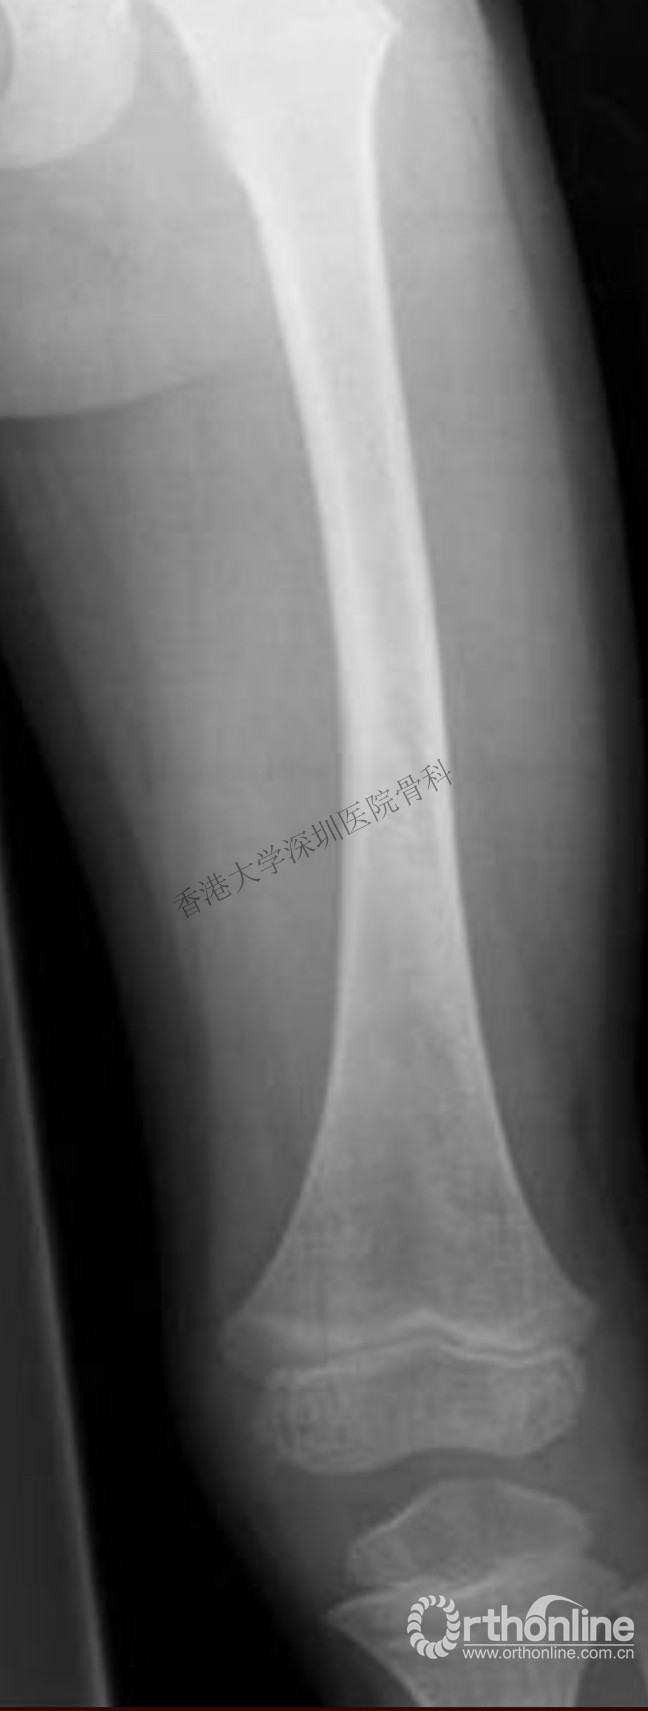

2岁儿童骨折,受伤时和1年后对比,塑型良好(受伤时)

2岁儿童骨折,受伤时和1年后对比,塑型良好(受伤1年后)

同时,我们也应该注意避免过度治疗,因为儿童骨骼具有良好的塑形能力,有时候并不需要解剖复位,很多对于成人无法接受的骨折移位,也可以得到良好的愈合和重塑。